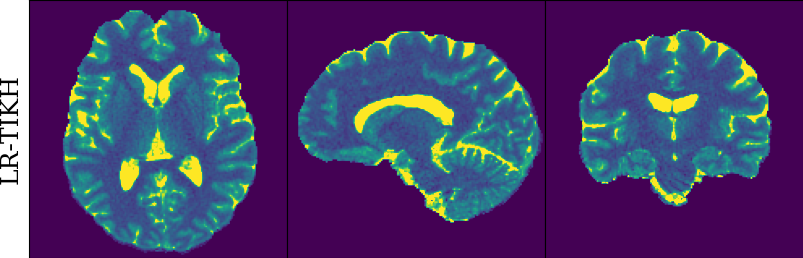

To monitor performance progress, we mapped TSMI to Q-Maps every five epochs. To mitigate the lengthy processing times associated with Dictionary Matching, we implemented a fully connected network to directly map TSMI to Q-Maps [5], significantly reducing processing time. However, for the final assessment, we employed DM on all techniques at the conclusion of the training process (epoch 500). We report in Table 1 the Mean Average Percentage Error (MAPE) of T1/T2 maps, and Peak Signal-to-Noise Ratio (PSNR) and Structural Similarity (SSIM) Index for T1/T2 and normalised PD. To accompany these metrics we also offer in Fig. 2 the reconstructed T1 and T2 maps for the different approaches.

The training and validation loss (Fig. 1) served as valuable guides for architecture and training design. To demonstrate this, we selected a subset of experiments in which we kept certain variables fixed and only modified the one under inspection. From Fig. 1 (a)-(d), MAPEs curves show there is a clear setting with the preferred performance. Specifically, from Fig. 1a, it is evident that using DRUNet yields a clear improvement over the original architecture. This could be attributed to the utilisation of residual units in addition to other architecture differences, such as the choice of upsampling operator (transpose convolution for DRUNet and trilinear for DIP). The choice of input (Fig. 1b) demonstrated a consistent pattern among the tested options, with low rank (conjugate gradient) initialiser marginally outperforming the others. Fig. 1cshows that by epoch 100, stochastic approaches exhibit lower reconstruction errors compared to non-stochastic methods. For example, adaptive LR with stochastic training yields a combined MAPE of 61.40% (17.09% T1 and 44.31% T2) vs. 213.69% (35.50% T1 and 178.19% T2) for the non-stochastic method. This fast convergence is due to adaptive LR and stochastic updates across coils. Despite similar execution times ( 34 min for stochastic with adaptive LR vs. 32 min for non-stochastic with fixed LR), the rapid error reduction makes StoDIP more attractive for training.. To assess the early stopping of DIP models, a key element, we present Fig. 1d. The original work by Ulyanov et al. [21] used 2k iterations, while Hamilton et al. [12] used 30k. In contrast, our settings show StoDIP achieving competitive performance in under 500 epochs (4k iterations) on the entire volume. However, StoDIP can overfit to k-space measurements, affecting reconstruction accuracy, and thus the iteration at which it stops could have a greater impact. We show that adding a spatial penalty term addresses overfitting and instabilities. This is supported by the maps in Fig.2, supplementary material Figures 1-3, and metrics in Table 1. StoDIP reconstructions lack aliasing artifacts, and the TV regularizer (StoDIP + TV) further improves Q-Map reconstruction by reducing checkerboard artifacts observed in StoDIP outputs alone.